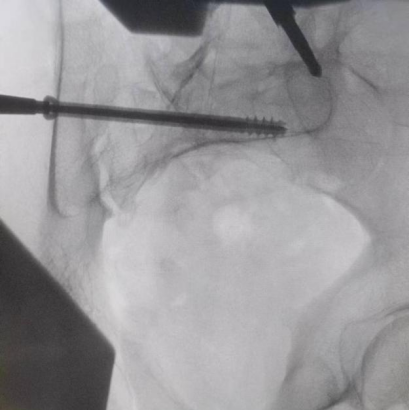

據(jù)了解,患者37歲,為高墜傷患者,入院合并顱腦挫傷、盆腔臟器出血、骨盆骨折多發(fā)傷患者。為最大限度降低手術(shù)風(fēng)險,同時給予患者滿意的手術(shù)療效,術(shù)前綜合評估患者病情,擬定行“天璣機器人”輔助定位下骨盆骨折微創(chuàng)手術(shù)。2月13日10時,手術(shù)正式開始。拉薩市人民醫(yī)院采集患者術(shù)中二維影像,通過骨科手術(shù)機器人擬定螺釘打入位置方向后,吳宏華主任完成手術(shù)設(shè)計,成功為該患者置入了一顆高難度骶髂螺釘,出血5ml,切口1cm。術(shù)后圖像顯示,螺釘位置及方向完全符合手術(shù)規(guī)劃,沒有一絲偏差,手術(shù)最終獲得圓滿成功。

圖為透視下見置入的骶髂螺釘,位置、長度精準(zhǔn),無絲毫偏差